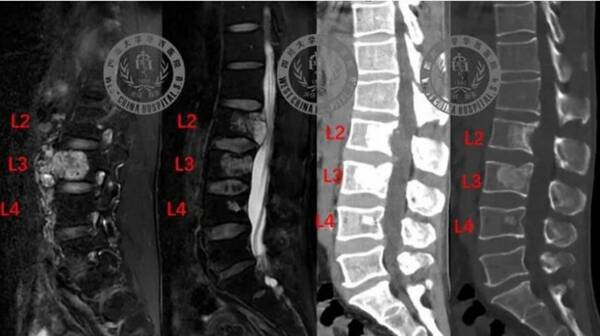

根據(jù)封面新聞,李先生今年47歲,7個月前,因為腰背部疼痛、右股部前外側(cè)麻木疼痛求醫(yī)。經(jīng)過一系列檢查發(fā)現(xiàn),李先生腰椎第2、3、4椎體長有脊索瘤。其中,腰2椎腫瘤向椎管內(nèi)生長,已經(jīng)壓迫椎管內(nèi)脊髓神經(jīng),產(chǎn)生馬尾圓錐損害;腰3椎腫瘤向腹腔內(nèi)生長,形成巨大的軟組織腫塊。脊索瘤是一種發(fā)生在顱底骨、脊柱骨和骶骨的罕見惡性腫瘤,發(fā)病率約為0.8/100萬人/年,未有效治療情況下5年生存率僅約為30%。因為脊索瘤容易發(fā)生局部浸潤和侵襲,對傳統(tǒng)放化療不敏感,手術(shù)治療是主要的治療方式。但術(shù)后極容易復發(fā),一旦復發(fā),往往會導致患者大小便失禁、下肢癱瘓甚至死亡。所以,初次手術(shù)能否完整切除腫瘤,是脊索瘤治療的關(guān)鍵。

3D打印人工椎體設(shè)計、實物及術(shù)后復查圖

為實現(xiàn)前方椎體有效重建,李濤教授團隊利用3D打印技術(shù)生產(chǎn)出個體化人工椎體。它根據(jù)患者解剖結(jié)構(gòu),進行個性化設(shè)計,完美契合上下正常椎體連接面。而3D多孔鈦合金打印設(shè)計,為人工椎體提供了足夠的生物力學強度。此外,特意設(shè)計了螺釘植入孔,可以將人工椎體假體與后方釘棒系統(tǒng)進行連接,構(gòu)成獨特的桁架結(jié)構(gòu),增加人工椎體穩(wěn)定性,使患者可以盡早下床康復訓練,實現(xiàn)像正常人一樣的生活和工作。據(jù)了解,這是西南地區(qū)首次將3D打印個體化長節(jié)段桁架結(jié)構(gòu)人工椎體,應(yīng)用于臨床實踐。

術(shù)后,李先生可以在醫(yī)護人員照護下佩戴腰部支具下床活動,逐步恢復。復查影像學顯示腫瘤無殘留,內(nèi)固定與人工椎體位置良好。李先生已于58日順利出院。